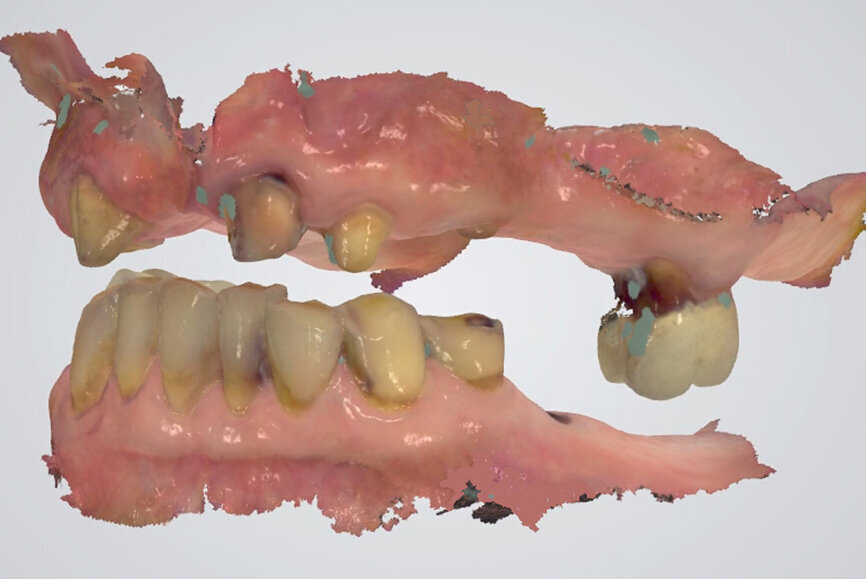

Fig. 18: TRIOS 3 software (3Shape) matching digital casts of arches to side view inter-arch scan (in light blue).

In contrast, digital recording has several advantages regarding efficiency and accuracy. The recording takes place without an interposed medium. The uploading of the digital casts in the software to the IC or CR position happens without the need for positioning of physical stone casts by an operator (technician). This ensures an accurate and efficient mounting in the virtual articulator. The direct digital occlusal recording is based on the intra-oral scanner software matching the digital casts of the arches to the inter-arch scan obtained from the side view of the arches (Fig. 18). The only noted disadvantage of the direct digital recording relates to the additional cost of acquiring an intra-oral scanner and the learning curve associated with operating one.